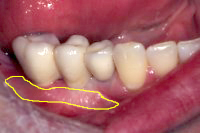

Zwei Implantate, hier bereits eingeheilt und mit den eingeschraubten Aufbauten versehen, werden in einer auf den Millimeter genauen Distanz gesetzt, um eine dreigliedrige Brücke aus Metallkeramik aufzunehmen (Abb. 1) und so die Lücke zu schliessen, die durch das Ziehen des Zahnes entstanden ist. Dann wird die Metallkeramikbrücke zementiert (Abb. 2).

- Vorgängig der Implantation habe ich in dem zahnlosen Kieferabschnitt ein freies Gingivatransplantat verpflanzt (Abb. 1, 2, gelbe Umrandung) (siehe Kap. Mukogingivalchirurgie), um für die Implantatpfosten optimale Zahnfleischbedingungen zu erhalten.